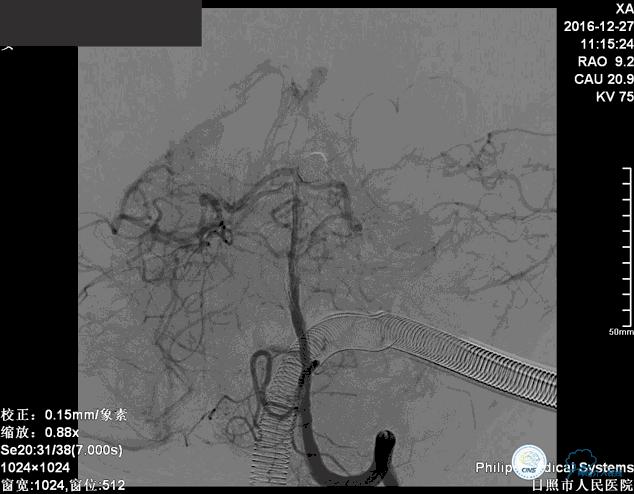

确诊:基底动脉顶端宽颈未破裂动脉瘤,动脉瘤大小约6mm×9mm,瘤颈约4毫米。

分别选择了7mmx30cm、6mmx30cm、2个4mmx15cm、3mmx8cm、2mmx8mm Target共6个弹簧圈进行栓塞。

这个病例我们采取了双微导管技术弹簧圈栓塞治疗。

这个动脉瘤是一个宽颈动脉瘤,动脉瘤的瘤颈和双侧的大脑后动脉关系比较密切。在进行栓塞治疗的时候要避免弹簧圈对双侧大脑后动脉以及小脑上动脉堵塞。

我们将两个微导管分别送入动脉瘤腔内,其中一个塑为u型,一个直头。两个微导管,一个位于动脉瘤较深的部位,1个位相对较浅的部位,交替进行栓塞。

前两个弹簧圈对动脉瘤的瘤颈和动脉瘤的后部进行了栓塞。成篮稳定以后,开始对动脉瘤的内部和前部进行栓塞。

这个手术的难点是在保证动脉瘤致密栓塞的同时,要保证双侧大脑后动脉的通畅。最终手术达到了较好的效果。